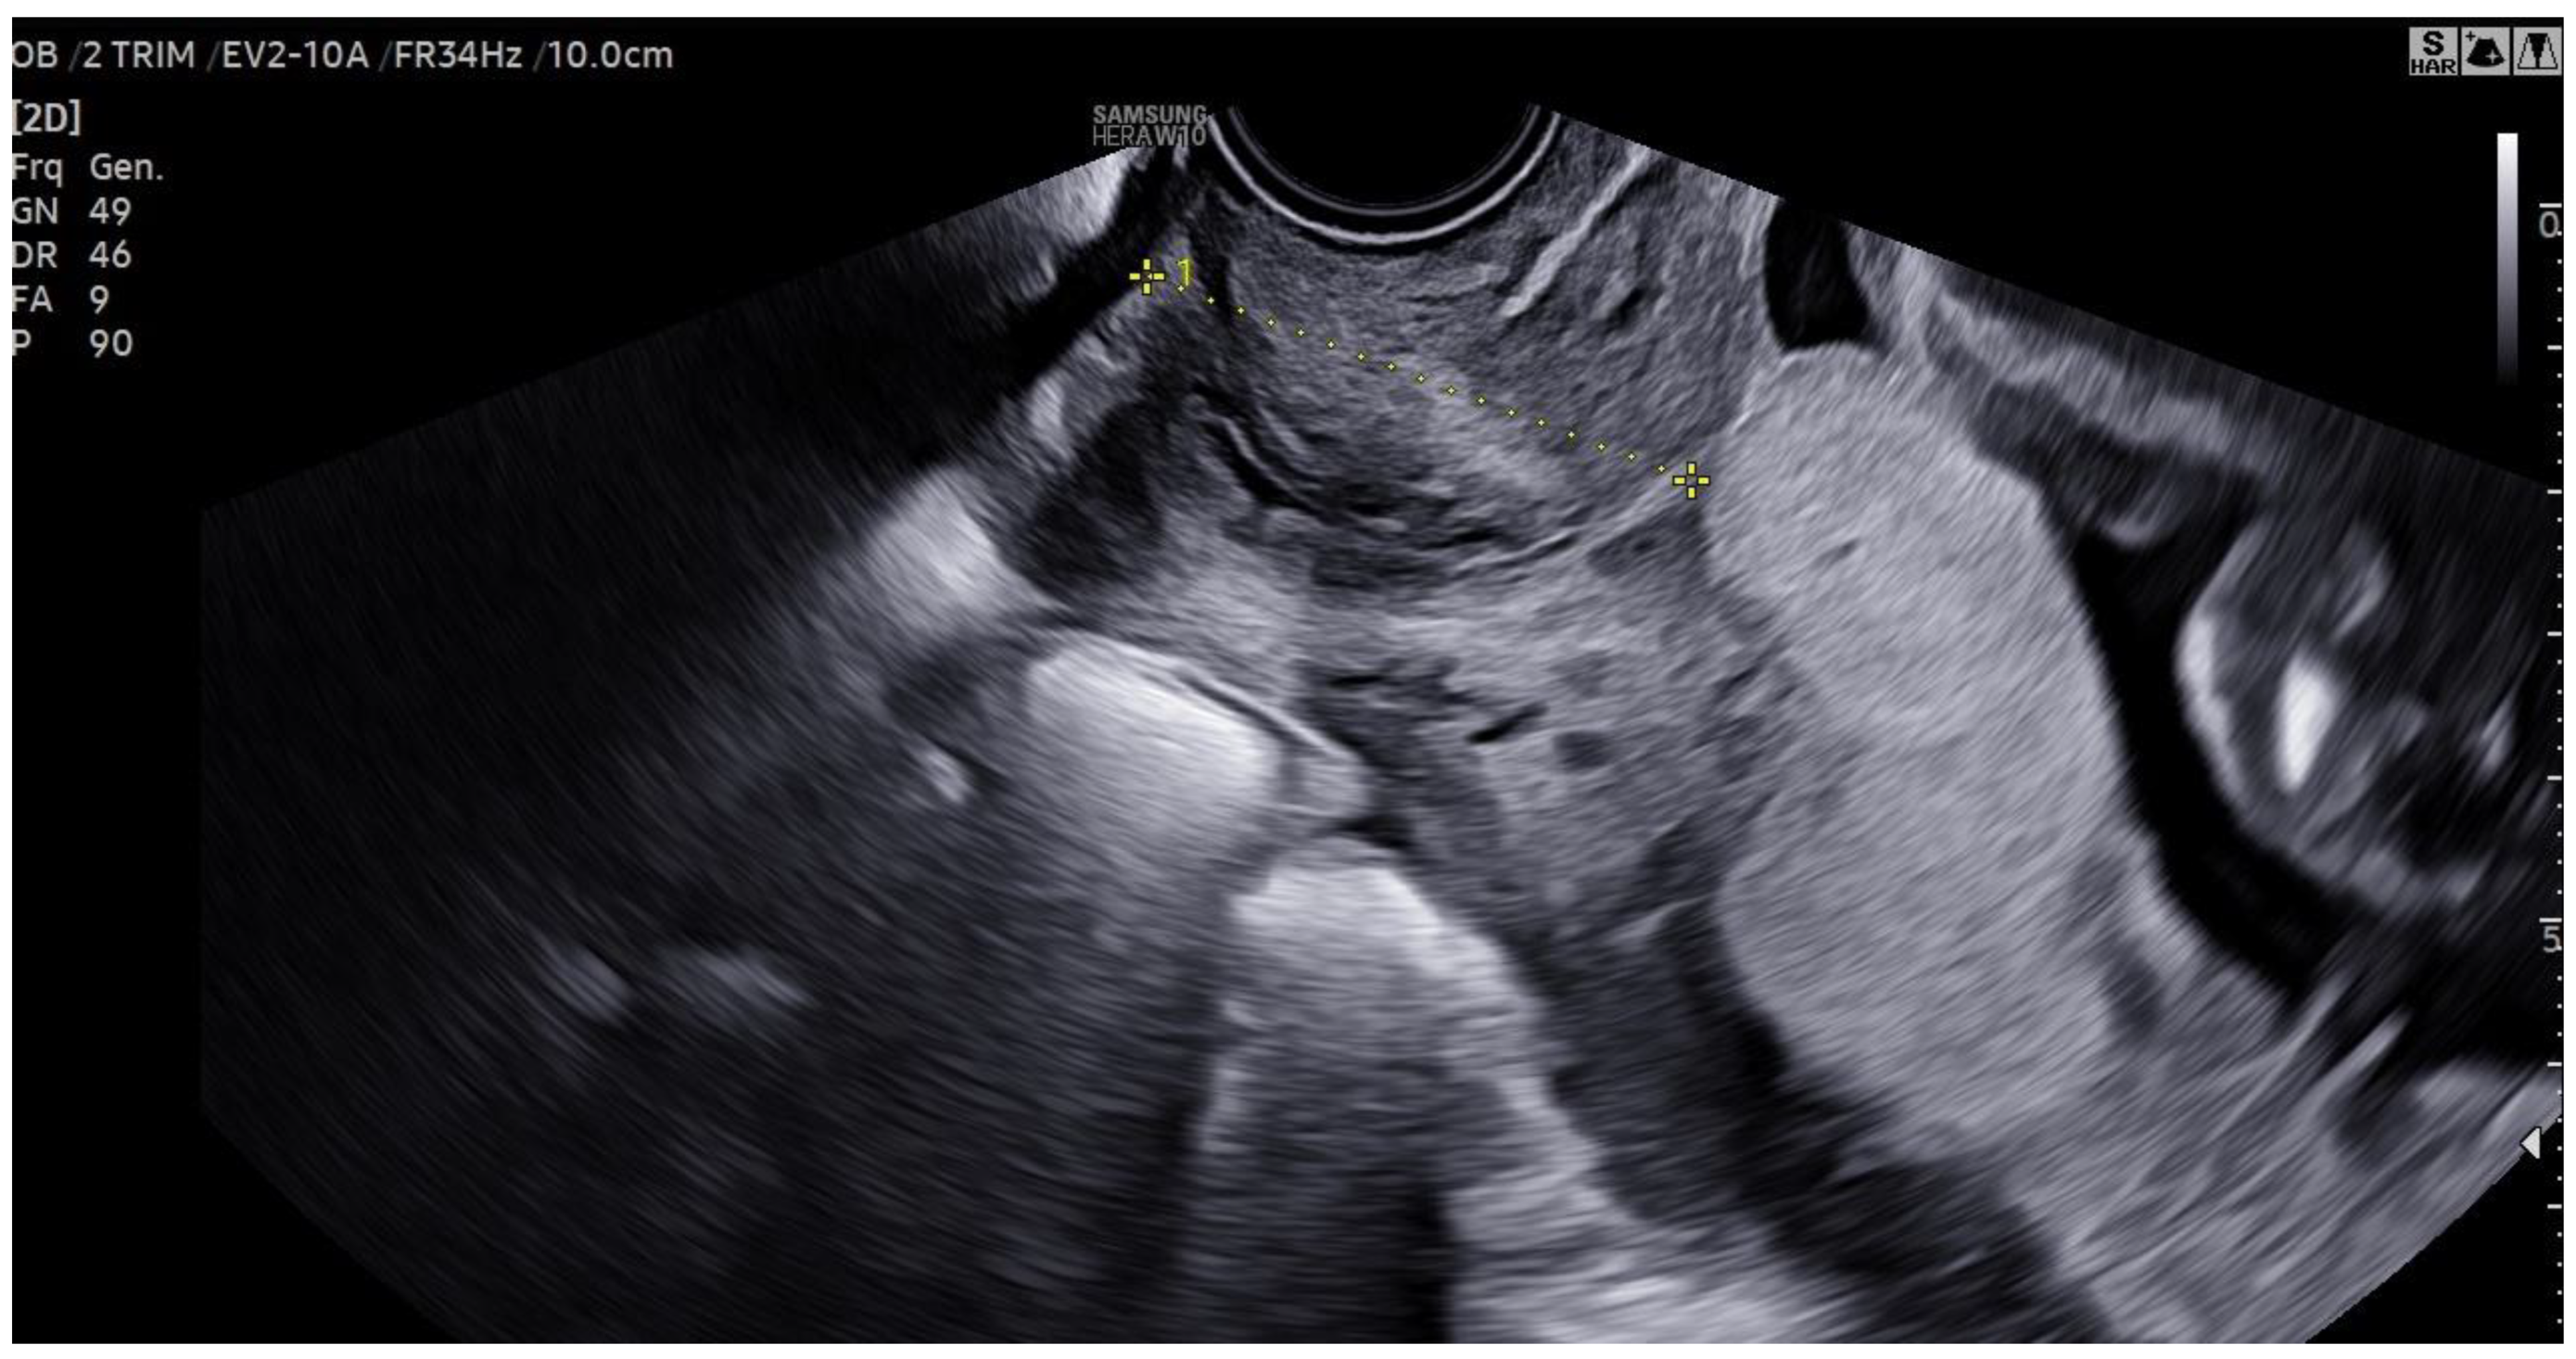

A 46-year-old woman underwent in vitro fertilization (IVF). Pregnancy progressed normally, with physiological development and appropriate fetal growth. In the third trimester, an ultrasound confirmed the diagnosis of a central placenta previa.

Figure 1. Transvaginal ultrasound confirming diagnosis of central placenta previa.